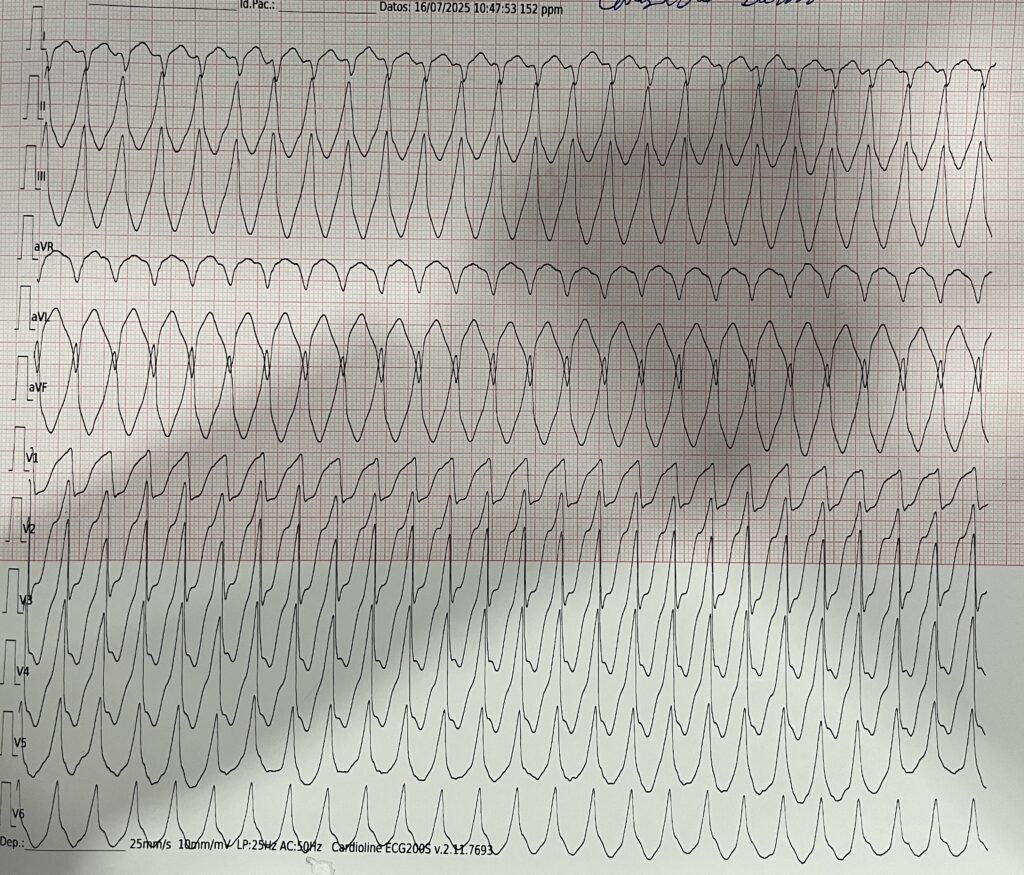

La frecuencia sigue subiendo hasta instaurarse una Taquicardia Ventricular (TV) monomórfica con pulso con 170 lpm y sin cambios clínicos en la paciente (conciente pero aletargada, tiempo de llenado capilar largo y presión arterial 106/68 mmHg).

Y, ahora, ¿qué hacemos? Pues dar manejo a la taquiarritmia inestable (ventanas clínicas de hipoperfusión tisular positivas en esta mujer). Veamos puntos clave recomendados en el Algoritmo de Taquicardia con Pulso2 del manual ACLS vigente al día de hoy:

En nuestra paciente la taquiarritmia generó alteración del estado mental y tiempo de llenado capilar distal, por lo cual realizar una cardioversión sincronizada estaba indicado. ¿Qué pasó después? Eso lo dejaremos para otra ocasión.